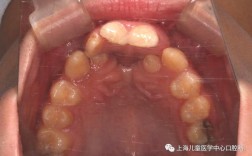

| 口内照片 | 上颌牙列正面 | 反光板置于上腭,镜头对准上颌牙列,显示全部牙齿及牙龈边缘。 | 观察牙齿排列、龋坏、牙周情况。 |

| 上颌腭侧 | 用拉钩牵拉上唇,镜头从上方拍摄上腭形态、系带位置。 | 评估上腭高拱、系带附着异常等情况。 | |